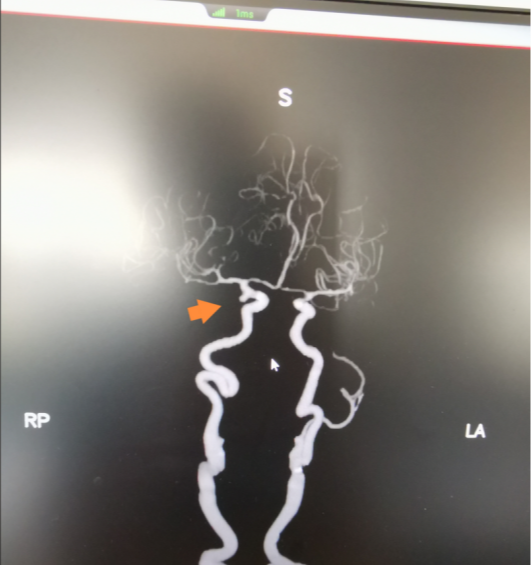

神经外科会诊后,高度怀疑颅内动脉瘤破裂出血,最终经CT血管造影检查(CTA),确诊患者为右侧后交通动脉瘤。

CTA影像